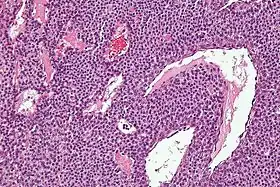

![]() صورة مجهرية لورم الكبي. صورة مجهرية لورم الكبي. | |

من الناحية النسيجية، تتكون أورام الكبي من شريان وريدي وارد، وجمع الوريد. يتم تعديل أورام الكبي من الخلايا العضلية الملساء التي تتحكم في وظائف تنظيم الحرارة للجسم الكبي والجلد. كما ذكر أعلاه، لا ينبغي الخلط بين هذه الآفات مع ورم جنيب العقدة العصبية، والتي كانت تسمى سابقا الأورام الكُلية في الاستخدام السريري الآن. الأورام الكبية لا تنشأ من خلايا الكبي، ولكن الورم جنيب العقدة العصبية ينشأ منها.